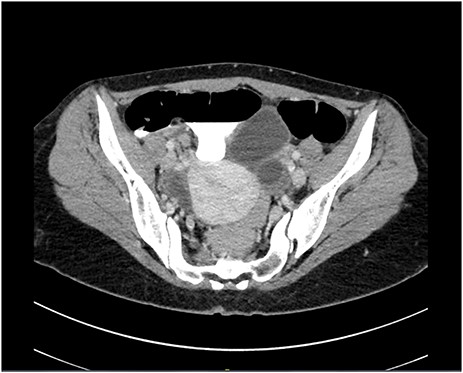

A pelvic ultrasound was normal. Gynecological causes of pain were ruled out. A computed tomography (CT) scan of the abdomen and pelvis demonstrated acute noncomplicated appendicitis (Fig. 1). WBC count was 9.42 x109/l with a neutrophil differential of 62.3%. The general surgery service was consulted for the findings. After a full history, physical examination and review of laboratory results and imaging, the patient was taken to laparoscopic appendectomy on the same day of presentation.

Computed tomography scan in a transverse cut demonstrating an inflamed appendix

The CT images in this case were reviewed again with a radiologist and it was confirmed that the features were consistent with acute appendicitis and there was no evidence suggesting the presence of diverticular disease. The reason for the patient’s persistent abdominal pain was not clear. While diverticular disease may be considered, the preoperative imaging did not suggest this. In any case, there is no increased incidence in colonic diverticulosis with appendiceal diverticular disease [2].